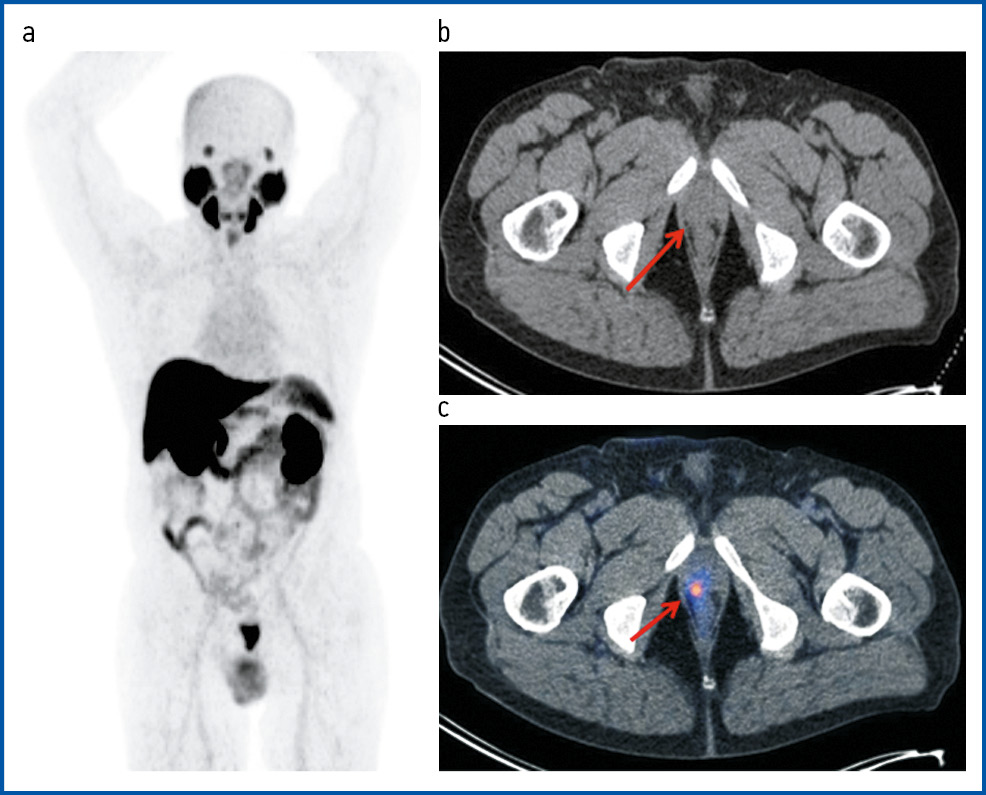

Рис. 4. Пациент А., 72 года. ПЭТ/КТ с 18F-PSMA. РПЖ, стадия pT3bN1M0G2. 3 + 4 = 7 по Глисону. Состояние после радикальной простатэктомии с тазовой лимфаденэктомией. Первично-множественный метахронный светлоклеточный ПКР. Латентный период – 26 мес. На MIP (a), аксиальной проекции КТ (b) и ПЭТ/КТ-исследовании (c) – состояние после радикальной простатэктомии. В области цистуретрального анастомоза справа визуализируется узловое образование с гиперфиксацией РФП, SUVmax 12,36 – рецидив.

Fig. 4. Patient A., 72 years old. PET/CT with 18F-PSMA PCa, pT3bN1M0G2 stage. Gleason score 3 + 4 = 7. State after radical prostatectomy with pelvic lymphadenectomy. Primary multiple metachronous clear cell RCC. The latency period was 26 months. On MIP, the axial view of CT, and pet/CT imaging, the state after radical prostatectomy was visualized. In the area of bladder-urethral anastomosis, a nodule with RPA hyper uptake was visualized on the right, SUVmax 12.36. Findings consistent with relapse.